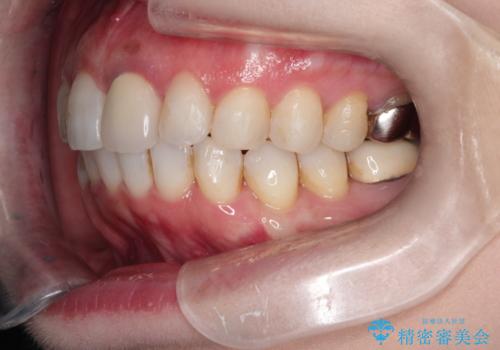

インビザラインによる非抜歯矯正 ガタガタな歯並びを整った歯並びへ

- 上下の全体的ながたつきが気になるとのことで来院されました。

マウスピースでの目立たない矯正を希望されたので、インビザラインでの治療となりました。

全体的に歯と歯の間にわずかに隙間を作り、歯を並べました。